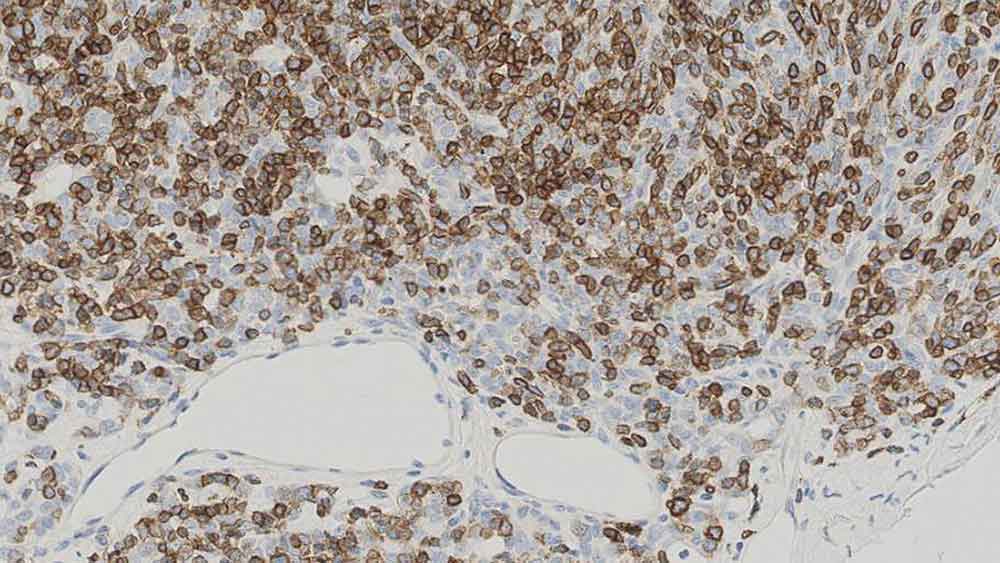

Human thymoma: immunohistochemical staining for CD1a. Note the neoplastic cells show a moderate to strong and distinct membrane staining reaction. CD1a: clone MTB1

CD1a is a protein of 43 to 49 kD expressed on dendritic cells and cortical thymocytes. CD1a antigen expression has been shown to be useful in differentiating Langerhans cells, powerful antigen presenting cells present in skin and epithelia, from interdigitating cells. Immunohistochemical studies for CD1a antigen have reported a reduction in epidermal Langerhans cells in graft versus host disease and the participation of CD1a antigen-positive dendritic cells in atherosclerotic lesion formation and asthmatic inflammation.

Clone MTB1 detects cortical thymocytes, Langerhans cells in epidermis, interdigitating cells of dermis and interdigitating cells of stratified squamous epithelium of tonsil. Clone MTB1 may also detect small focal groups of lymphocytes outside the germinal centers of tonsil indicating a cross-reaction with CD1b antigen.